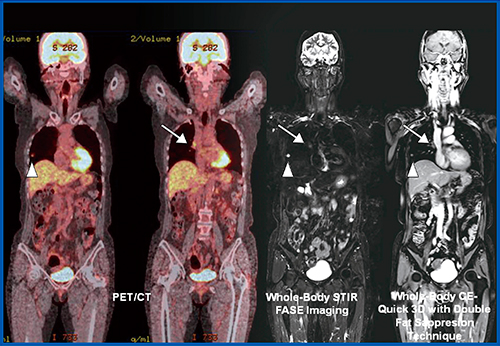

肺がん患者の臨床病期診断における有用性は,1991年のRadiologic Diagnostic Oncology Groupによる論文以来,MRIはその組織コントラストの高さから縦隔浸潤,胸壁浸潤に関してのみ有用性が示唆されてきた3)。また,2000年以降には1.5T MR装置によるCE-MR angiographyなどを用いたT因子診断の臨床応用が模索されたこともあったが,現在ではN因子およびM因子診断における有用性が知られており,主としてNおよびM因子診断に用いられている4)〜6)。そして,2007年以降はShort TI inversion recovery(STIR)法やDiffusion-weighted MR imaging(DWI)法を含めた全身MRI(Whole-body MR imaging:WB-MRI)のM因子診断を中心とした有用性の示唆がなされている7)〜11)。これらの手法による診断能は,PETやPET/CTに比して同等あるいは有意に高いことが示唆されている。一方,これらの手法は,3T MR装置においてもPET/CTと同様に,NおよびM因子診断において有用であることが示唆されている7)〜11)。したがって,3T MR装置においても,今後はNおよびM因子診断においては1.5T MR装置と同様に臨床応用が進むと考えられる(図2)。また,近年では本手法を肺がん術後再発の検索においても応用可能であり,PET/CTや通常の画像診断による転移検索検査と比してより特異度や正診率が高いことも示唆されており,PET/CTや通常の画像診断による転移検索検査の代用になる可能性が示唆されている12)。

図2 73歳,女性,肺腺癌患者(pT1aN1M0:pStage IIA)のFDG-PET/CT

およびWB-MRI

PET/CTおよびWB-MRIにおけるSTIR fast advanced spin-echo(FASE)法および脂肪抑制造影Quick 3D法において,原発巣(▲)および肺門部リンパ節転移(→)を明瞭に描出している。